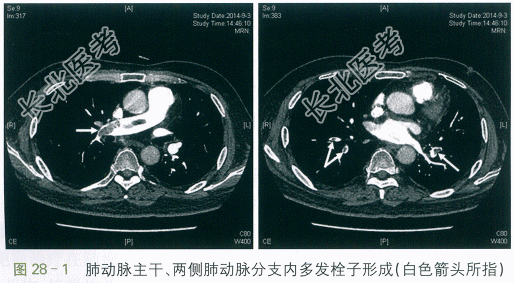

患者,男性,52岁。因"右下肢肿胀10余天,胸闷1周伴痰血"入院。患者10余天前出现右下肢肿胀,较左侧增粗,非凹陷性,表面皮肤无皮疹、破溃,未予重视。1周前自感胸闷,伴痰中带血3次,无发热、胸痛、呼吸困难、心悸等。2天前自感胸闷加重,遂至我院门诊就诊。查血常规:WBC9.93×109/L,Hb129g/L,PLT128×109/L。X线胸片示:两肺未见活动性病变。D-二聚体:15.78mg/L。进一步行CT肺动脉造影示:肺动脉主干、两侧肺动脉分支内多发栓子形成。遂予以收治入院。

CT肺动脉造影示:肺动脉主干、两侧肺动脉分支内多发栓子形成(见图28-1)。